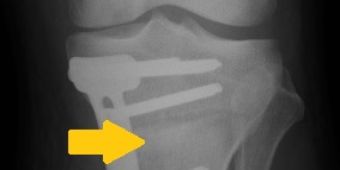

hto

Achskorrektur mit Öffnen des Unterschenkels (Pfeil) und Fixierung mit einer Platte. © Asklepios

• Erwachsene: bei bereits geschlossener Wachstumsfuge muss im Gegensatz zu Kindern und Jugendlichen der Unter- oder Oberschenkelknochen je nach Ort der Fehlstellung geöffnet und mit einer Platte und Schrauben wieder in der richtigen Position befestigt werden (Bild).